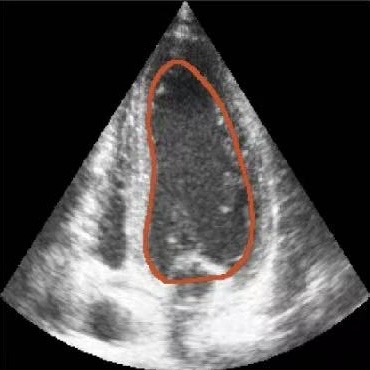

Challenges in Echocardiography Segmentation 超声心动图视频分割面临的挑战

Echocardiography segmentation faces several challenges such as low contrast, speckle noise, and signal dropout. 超声心动图视频分割面临着诸如低对比度、斑点噪声和信号丢失等多重挑战。

Figure 2. Illustrative challenges for echocardiography video segmentation: (a) speckle noise, (b) indistinct or blurred contours, and (c-f) the substantial changes in the target’s shape and scale throughout the cardiac cycle. 图 2. 超声心动图视频分割面临的典型挑战:(a) 斑点噪声,(b) 轮廓不清或模糊,以及 (c-f) 在整个心动周期中目标的形状和尺度发生的显著变化。